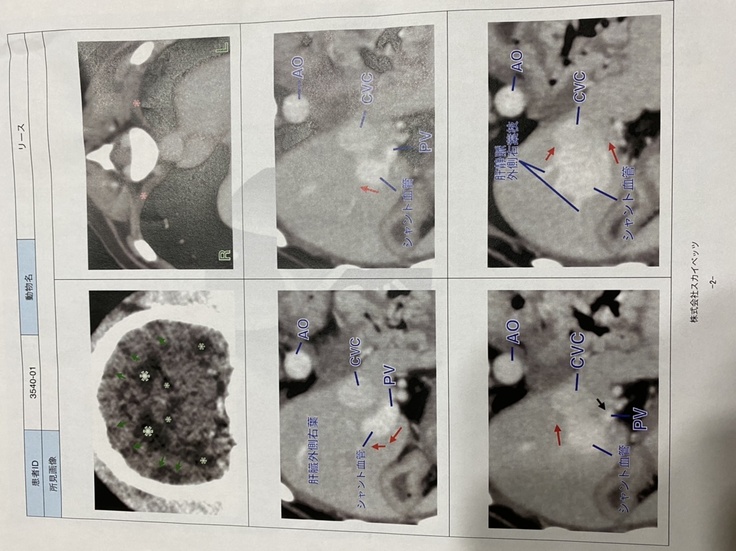

〜先天性門脈体循環シャントとは〜

(PSS:Portosystemic Shunt)略されて門脈シャントやPSSとも呼ばれています。原因としては遺伝的素因が強いといわれています。

本来、腸(消化管)から吸収された栄養や毒素(アンモニア)は門脈という静脈血管から肝臓に運ばれ処理されます。

しかし、門脈シャントの犬は、門脈血管の途中に枝分かれしたシャント血管(図B:赤い血管がシャント血管)ができてしまっているので、そちらに栄養や毒素が流れ込んでしまうのです。

肝臓の血管はフィルターのように細くなっているので流れやすいシャント血管の方にどうしても流れ込んでしまいます。

この門脈と全身の静脈の間をつなぐ余分な血管(シャント)が存在することにより、肝臓で無毒化されるべき有害物質が処理されないまま直接全身を回ってしまい、さまざまな症状が引き起こされる病気です。

正常であれば、胃腸からの血液は門脈(もんみゃく)と呼ばれる専用の血管を通じて肝臓内に入り、そこで解毒を受けて全身を巡る血液循環、すなわち「体循環」に合流します。

しかし、シャントにおいては門脈から体循環につながる血管に近道が出来てしまっているため、解毒を受けていない血液がそのまま体循環に混入してしまいます。

その結果、有害な物質が体の各所に届くようになり、様々な弊害を生み出すと同時に、肝臓が栄養失調に陥って小さく萎縮してしまいます。

リース君の場合、2.1㎝にもなる異常血管になるため最低3回は手術が必要と言われました。